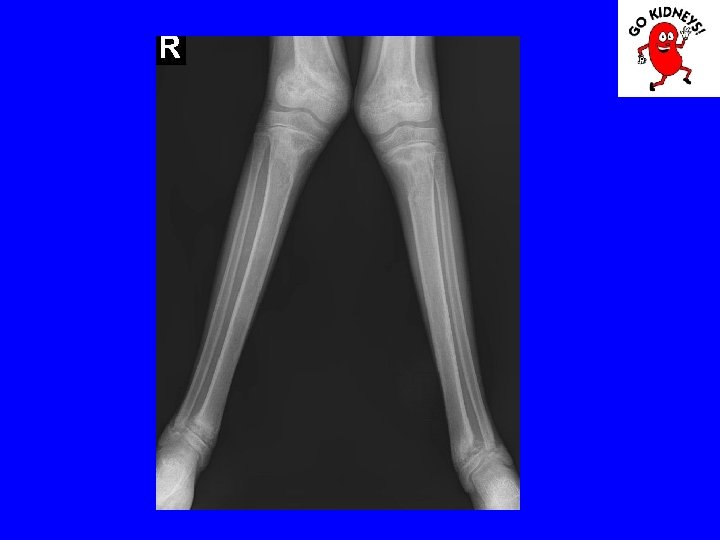

• Diagnosis of renal osteodystrophy 2. radiological changes - subperiosteal resorption of bone is visible in the proximal and middle phalanges, femoral neck and proximal portion of the tibia. The bone resorption is proportional to the aggravation of hyper. PTH. - erosion and disappearance interalveolare jaw septa are signs of severe secondary hyperparathyroidism. - radiological signs of rickets are the lack of bone matrix mineralization in the knees and punches. - osteosclerosis is less obvious in children, in particular in the vertebral body.

Diagnosis • Physical examination may be noted: - delays in growth - presence of signs of rickets or pathological fractures, - high BP. • Laboratory tests show that: - anemia normochromic, normocytic, aregenerativa. - Nitrogen retention and decreased creatinine clearance - metabolic acidosis, hyperkalemia, hyperphosphatemia, - hypocalcemia, hyponatremia - proteinuria or hematuria urinary sediment suggesting glomerular disease old. - low urinary density suggesting a chronic kidney ailment. • Renal ultrasound may show decreased volume of the kidneys • Bone radiography signs of renal osteodystrophy. • Retrograde cystography may help in the diagnosis of reflux nephropathy. • Radioisotope study can give differentiated data for each kidney function.